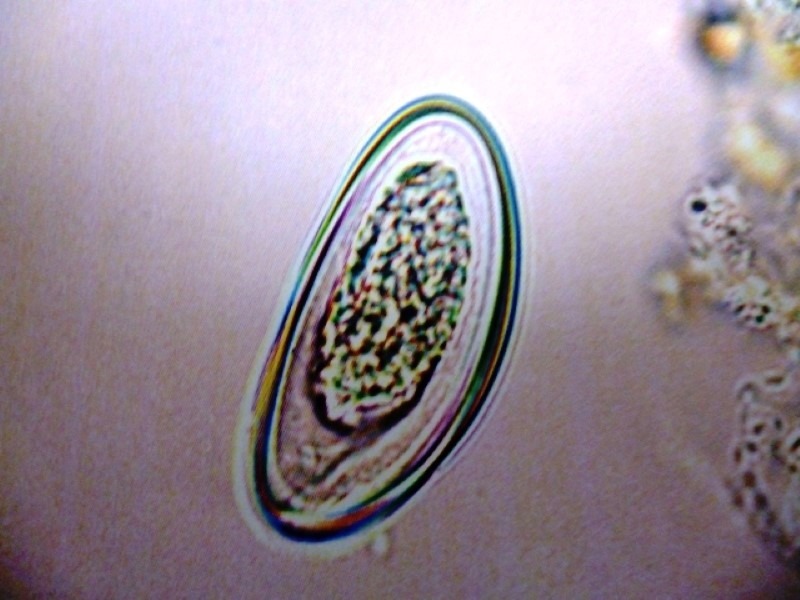

The pinworm, also known appropriately as the seatworm in the United Kingdom, is another parasite that resides in the digestive tract. Humans become infected by ingesting the eggs which are invisible to the naked eye but are quite resilient, and can be spread easily by numerous means. The adult worms mate in the small intestine, which is usually followed by the death of the male. The female then migrates down through the digestive system until it emerges and lays its eggs on the anus, which often leads to itching and irritation. Oftentimes the tiny eggs are then spread around through contact with other objects, with the lucky ones find their way onto things that end up being eaten or put in someone’s mouth. Some eggs actually reverse direction and make their way back up into the digestive tract after hatching where the cycle begins again.